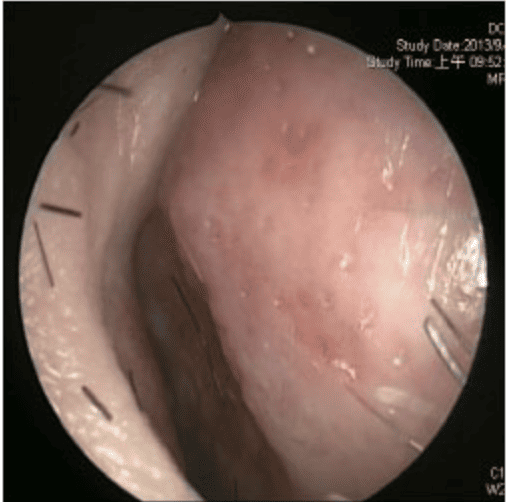

透過內視鏡檢查時,發現F先生右側尾端鼻中隔彎曲,幾乎貼近側壁,而且右側鼻阻力圖呈水平,代表F先生右側鼻空肌膚不能呼吸。鼻中隔軟骨扭曲變形、左上側軟骨凹陷萎縮,我們團隊先進行鼻部結構拆解及鼻中隔成形手術,再利用取下的鼻中隔軟骨進行重建,同時進行右側截骨術(Osteotomy),從根本矯正歪斜的鼻樑。